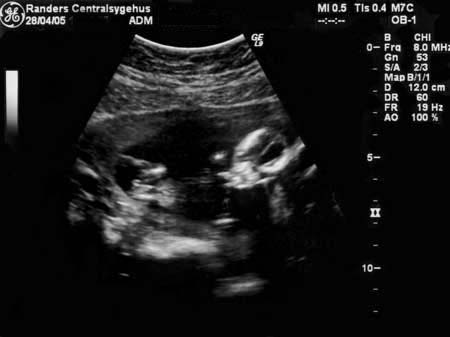

uge 30+0

Så er der simpelthen kun 10 uger til vi skal se vores lille søn..